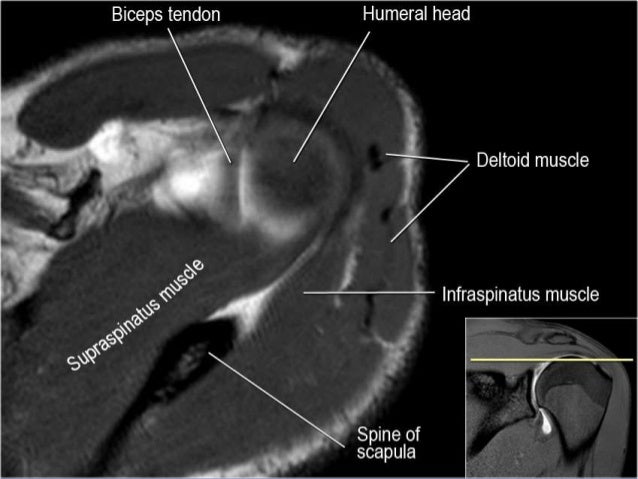

41+ Sagittal Mri Shoulder Anatomy. Normal anatomy, variants and checklist. Notice rotator cuff muscles and look for atrophy.

In the coronal oblique plane, slices are made parallel to the tendon of the supraspinatus muscle, starting from the posterior to the. For an accurate evaluation is essential to know the normal anatomy and variants to avoid the misdiagnosis of a pitfall as pathological condition. In this article, we shall look at the anatomy of the shoulder joint and its important clinical correlations.

Robin smithuis and henk jan van der woude. This mri shoulder cross sectional anatomy tool is absolutely free to use. Highest section shows supraspinatus muscle followed posteriorly by infraspinatus muscle & teres minor & its tendons. The use of mr for the diagnosis of shoulder lesions is well established, as well as mr arthrography for the diagnosis for shoulder instability and microinstability.